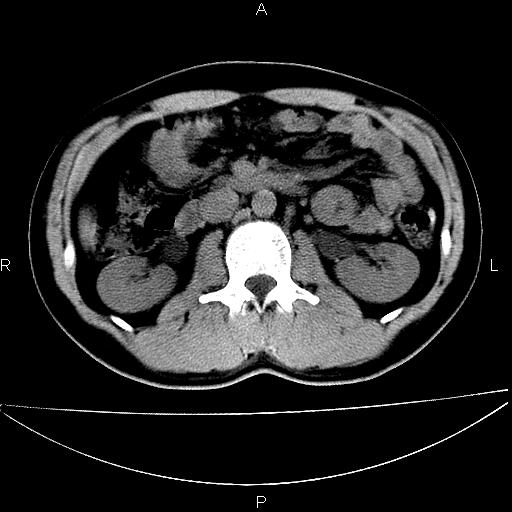

男 25岁 自述 尿频尿急,排尿困难20多天.无腰痛, b超说左肾盂轻度积水,左输尿管上端扩张.未见结石影. ct我看双侧肾盂轻度积水,双输尿管上端都扩张,大家看看能看见结石吗?

考虑肾外肾盂 前列腺轻度肿大 密度欠均 考虑炎性改变

箭头所指不是输尿管,壶腹型肾盂。

肾外肾盂,必要时+c